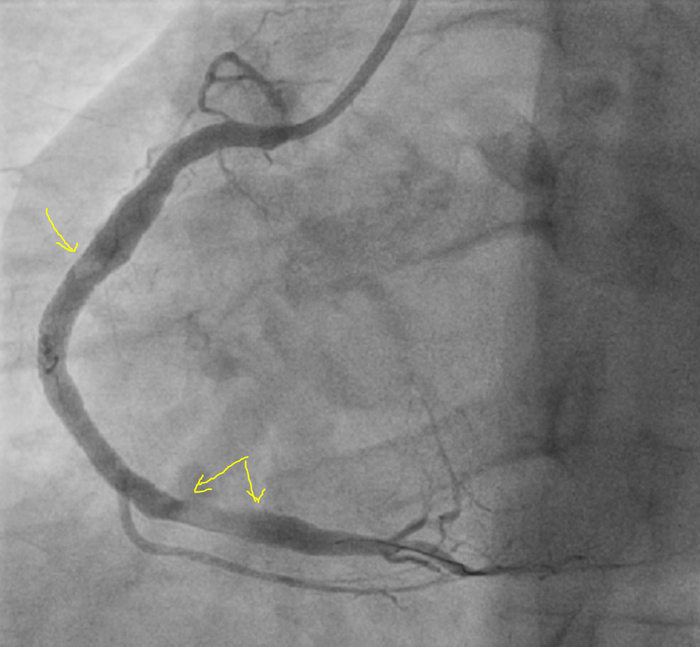

Ко второму курсу училища( училища, а не универа) я уже читал ЭКГ. Все основные случаи инфарктов, аритмий и блокад. Изучал все пленки ЭКГ.